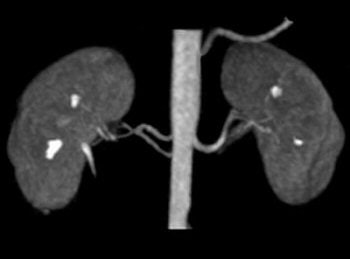

![]() |

| Above, noncontrast subclavian MRA on 1.5-tesla scanner (Achieva). Below, noncontrast renal 3D TFE MRA with inversion recovery of stenosis of the renal arteries using navigator gating during free breathing. Images courtesy of Philips Medical Systems North America, Hyogo Brain and Heart Center, Hyogo, Japan (above), and Dr. Marcus Katoh, University of Aachen, Germany (below). |